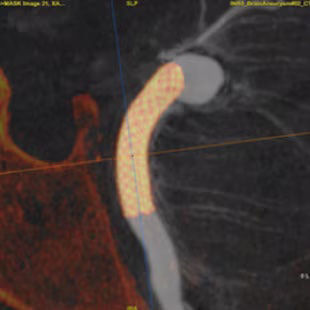

Plan

Segment and size the anatomy of interest in CBCT.1 Plan the stent positioning on the 3D model and prepare 3D landmarks to help guide the deployment.

With 3DCT HD and Virtual Dilution visualize the relationship between your device and vessel with robust image quality and without changing your contrast injection protocols. 3,4

vessel-assist-access-neurointerventional-ci-en